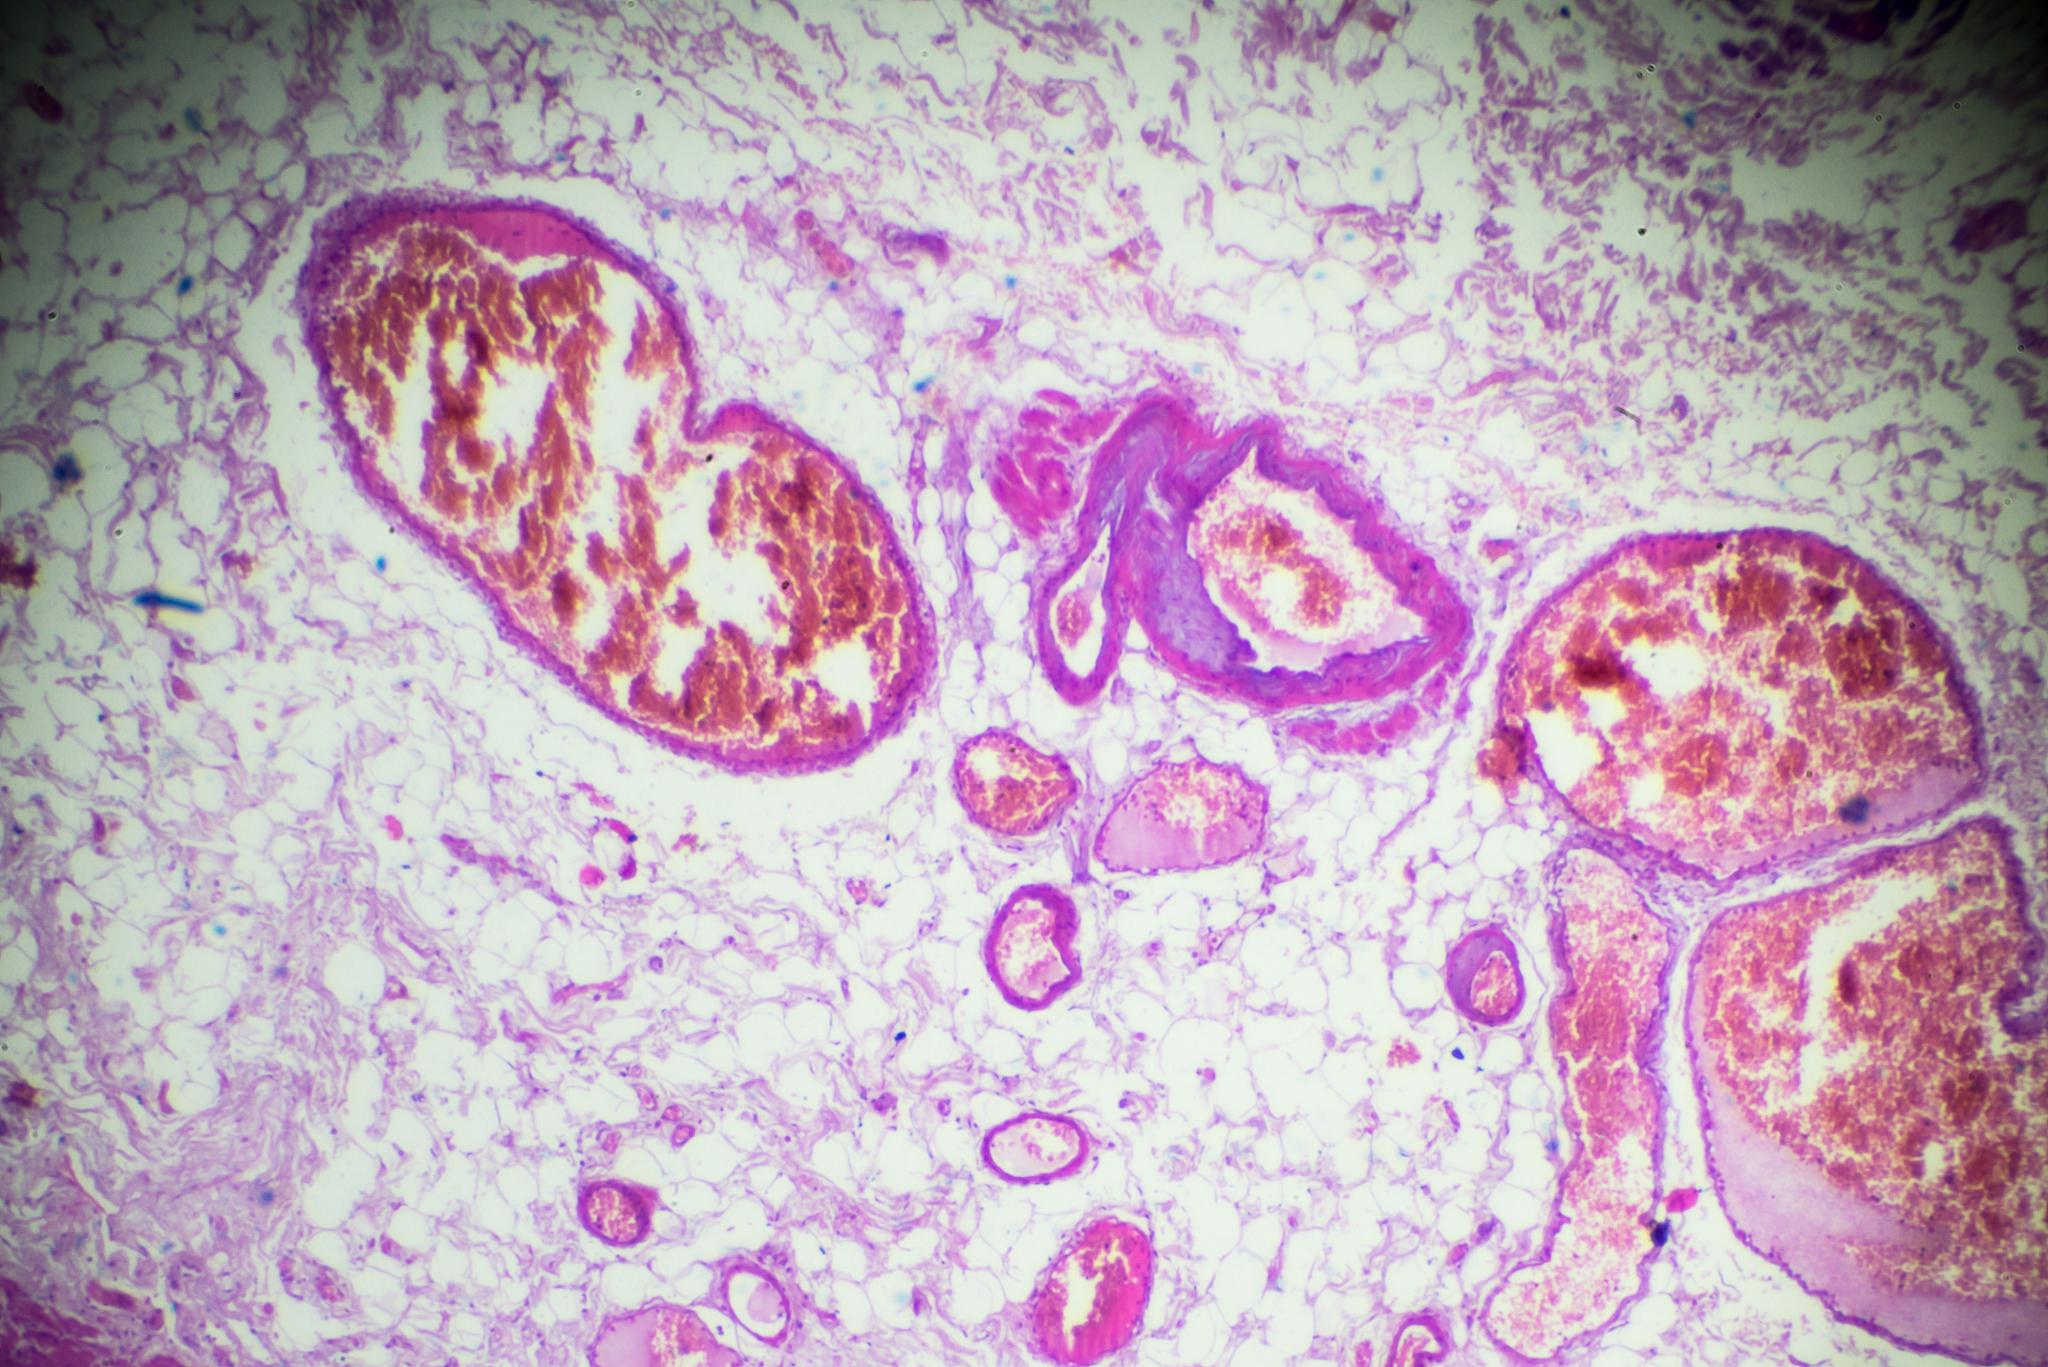

胃癌的发生发展是一个复杂的多因素过程,涉及环境、感染、基因和表观遗传等多个方面。近年来,对微晶状细胞抑制细胞因子-1 (MIC-1) 在肿瘤中的作用研究逐渐成为热点。MIC-1属于转化生长因子-beta超家族,由巨噬细胞分泌,具有抑制和促进的双重作用,参与多种应激反应。

研究发现,MIC-1在多种肿瘤细胞中高表达,其水平与肿瘤的发生、发展密切相关,参与肿瘤细胞增殖、侵袭和转移过程[5-7]。然而,MIC-1在肿瘤中的作用呈现出明显的阶段特异性:

- 早期抑癌作用: 文献报道表明,在癌症早期,MIC-1发挥着抗肿瘤的作用,可以看作是一种负性生长调节因子。肿瘤抑制基因p53能够靶向MIC-1的激活区域,诱导其表达增加,进而导致细胞周期阻滞和凋亡[9]。* 后期促癌作用: 一些研究表明,随着肿瘤微环境的变化,MIC-1的表达在癌症中后期逐渐升高,并与癌症进展、侵袭深度和淋巴结转移密切相关[10-22]。

已有研究表明,胃癌患者血清中MIC-1的水平与胃癌进展呈正相关[23],但其具体作用机制仍不清楚。构建MIC-1过表达细胞系为研究其在胃癌发生发展中的生物学功能和相关机制提供了新的思路。